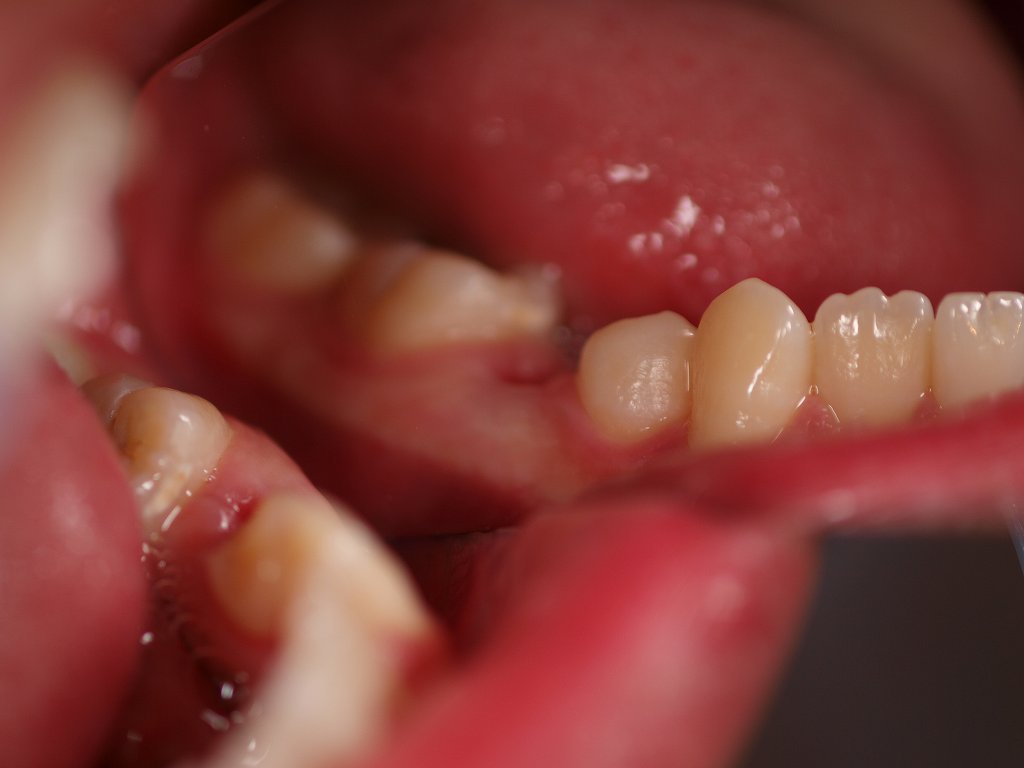

ブログ一覧|広島市安佐南区の歯科医院 ブログ一覧 トップ ブログ一覧 お知らせ スタッフブログ ブログ一覧 スタッフブログ 2018/03/26 3月24日 ソフトボールの卒団式 119勝 13敗 9分 優勝16回 間違いなく県下で最強のチームだったと思います。 スタッフブログ 2018/03/26 3月24日 ソフトボールの卒団式 119勝 13敗 9分 優勝16回 間違いなく県下で最強のチームだったと思います。 スタッフブログ 2018/03/26 3月24日 ソフトボールの卒団式 119勝 13敗 9分 優勝16回 間違いなく県下で最強のチームだったと思います。 2018/03/24 口腔内にてシェード合せを行っています。 この操作が仕上がりの明暗を分けます。 2018/03/24 口腔内写真は大事です。 その当時の状態を鮮明に記録しておくことは患者さんとこれからもかかわって一緒に老いていくうえで大切な情報です。 2018/03/24 ジルコニアブリッジの7時間半かけてのシンタリング後、模型合わせ、内面調整ポーセレン築造へ 焼成中の画像になります。 焼き上げると青色のポーセレンもこんな色調を作り出していきます。 2018/03/24 口腔内にて合せたところです。 色調もしっかりと合ってるかと思います。 2018/03/24 ジルコニアブリッジの7時間半かけてのシンタリング後、模型合わせ、内面調整ポーセレン築造へ 焼成中の画像になります。 焼き上げると青色のポーセレンもこんな色調を作り出していきます。 << 1 2 3 4 5 … 699 700 701 702 703 … 870 871 872 873 874 >> Web診療予約 初めての方へ 選ばれ続ける理由 院内設備について 歯が痛いしみる一般歯科 歯がぐらぐらする歯周病 健康な歯を保ちたい予防歯科 子供の虫歯予防をしたい小児歯科 銀歯をセラミックに審美歯科 白い歯を目指しませんか?ホワイトニング 矯正専門医がいるので安心矯正歯科 抜けた歯を補いたいインプラント・入れ歯 医院案内 スタッフ紹介 メリィハウス歯科クリニックオフィシャルホームページ ラベンダー歯科クリニックオフィシャルホームページ お知らせ・ブログ ホーム 診療科目 一般歯科 歯周病治療 予防治療 小児歯科 審美治療 ホワイトニング 矯正歯科 入れ歯・インプラント マウスピース矯正 初めての方へ 院長・スタッフ 設備紹介 医院案内・アクセス メニューを閉じる